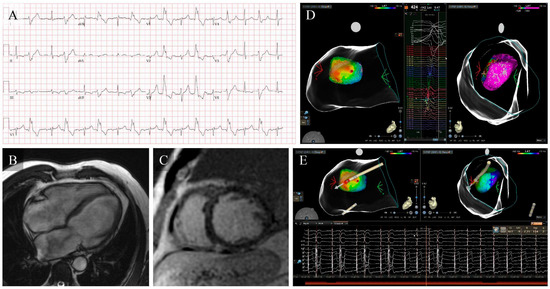

Premature Ventricular Complex-Induced Cardiomyopathy, a Review: Current Insights, Diagnostic Challenges, and Therapeutic Strategies

Premature Ventricular Complexes (PVCs) are among the most frequent ventricular arrhythmias observed in daily cardiology practice. Although often benign, sustained high ectopic activity can result in left ventricular dysfunction known as PVC-induced Cardiomyopathy (PVC-CMP), a condition that is frequently reversible when the arrhythmia [...] Read more.

Premature Ventricular Complexes (PVCs) are among the most frequent ventricular arrhythmias observed in daily cardiology practice. Although often benign, sustained high ectopic activity can result in left ventricular dysfunction known as PVC-induced Cardiomyopathy (PVC-CMP), a condition that is frequently reversible when the arrhythmia is effectively suppressed. The underlying mechanisms are multifaceted, involving electromechanical dyssynchrony, contractile inefficiency, abnormal calcium cycling, neurohormonal activation, and progressive structural remodeling. The likelihood of developing PVC-CMP varies among individuals and is influenced by electrophysiological and structural factors. Diagnosis relies on prolonged rhythm monitoring, comprehensive multimodality imaging, and demonstration of ventricular recovery after reducing the ectopic burden, which, in turn, confirms causality. Over the past decade, major advances in electrocardiographic mapping, cardiac imaging, and ablation therapy have transformed this field, demonstrating excellent efficacy and safety profiles. In parallel, artificial intelligence and computational mapping are emerging as powerful tools for prediction and procedural guidance. Recognition of PVC-CMP as a distinct, treatable cardiomyopathy highlights the importance of early detection and individualized therapy, offering the prospect of complete functional recovery and the prevention of heart failure progression. Full article

Figure 1